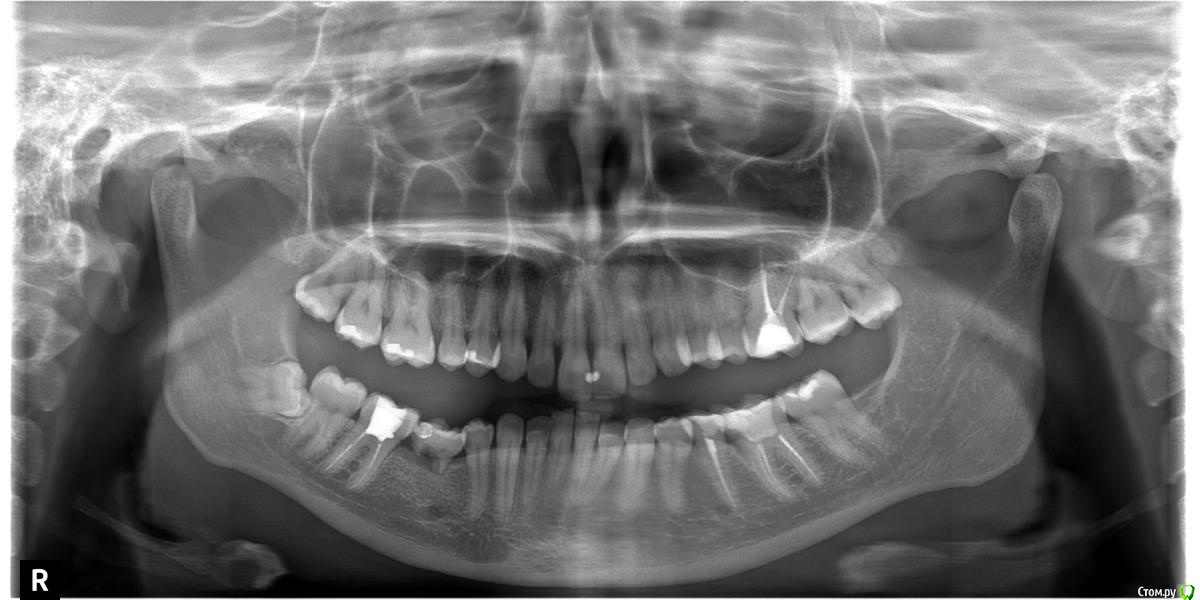

Ghera Опубликовано 5 января, 2016 Поделиться Опубликовано 5 января, 2016 Здравствуйте. Имею левый нижний шестой зуб, который начал сверху крошиться. У него длинная и довольно печальная история. Ок. 2003 года был впервые депульпирован (не помню чем, но не резорцин), в 2008 году на корне обнаружилась гранулема, перелечен, запломбирован с помощью метапекса. Пломба большая и неудачная, получился десневой карман.Теперь стенки зуба вокруг пломбы потихонечку сверху выкрашиваются (год назад надломилась половина язычной стенки под десну, удалили, но тогда не было времени прицельно им заняться).Зуб не болит и вообще никак не беспокоит. Что с ним делать? Удалять и ставить мост? Перелечивать каналы и коронку на вкладке? Имплантв прямом смысле не по зубам... Ссылка на комментарий

DmitrySH Опубликовано 5 января, 2016 Поделиться Опубликовано 5 января, 2016 Убрать пломбу, оценить то что осталось и тогда уже принимать решение. На данном снимке ситуация не выглядит критичной, но в полости рта может быть другая картина.А вот шестой внизу справа, его уж точно удалять.+восьмые зубы надо бы удалять( вверху слева может давать болезненные ощущения, там глубокая кариозная полость) Ссылка на комментарий

red_butler Опубликовано 6 января, 2016 Поделиться Опубликовано 6 января, 2016 Убрать пломбу, оценить то что осталось и тогда уже принимать решение. На данном снимке ситуация не выглядит критичной, но в полости рта может быть другая картина.А вот шестой внизу справа, его уж точно удалять. Это вроде молочная пятерка Ссылка на комментарий

IvanK Опубликовано 6 января, 2016 Поделиться Опубликовано 6 января, 2016 @Ghera, консультация ортодонтаСправа молочный зуб - удаление, имплантация18,28,48 - удаление26,36,36,46 - консультация ортопеда 1 Ссылка на комментарий

Ghera Опубликовано 6 января, 2016 Автор Поделиться Опубликовано 6 января, 2016 Так точно, молочная пятерка, леченная еще при Горбачеве. А если ее имплантировать - там кость не рассосалась? Ссылка на комментарий

red_butler Опубликовано 6 января, 2016 Поделиться Опубликовано 6 января, 2016 Так точно, молочная пятерка, леченная еще при Горбачеве. А если ее имплантировать - там кость не рассосалась?По высоте кость есть 1 Ссылка на комментарий